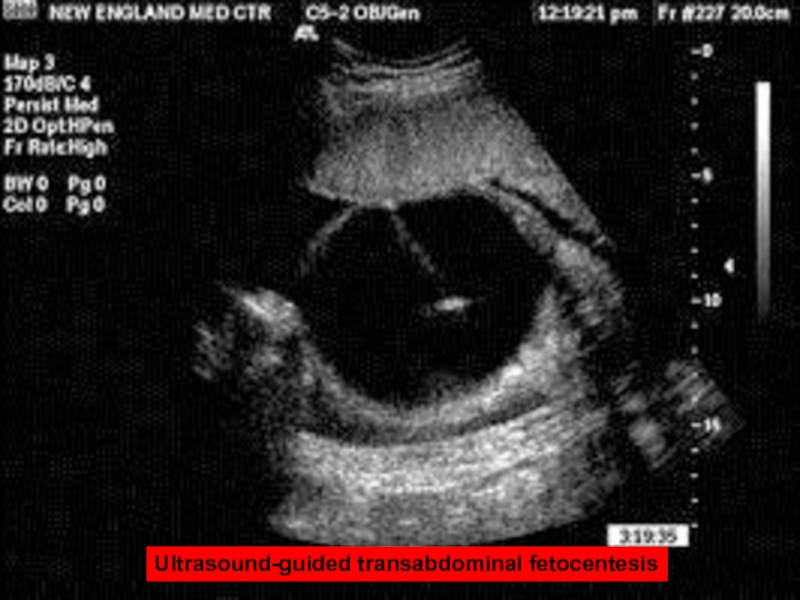

Слайд 57Ultrasound-guided transabdominal fetocentesis